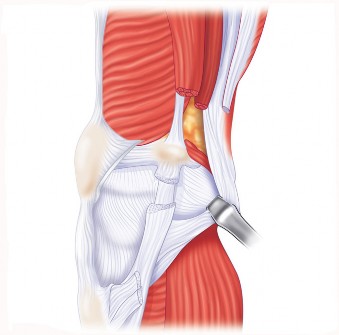

هذه الجراحة ليست مجرد استبدال للمفصل التالف، بل هي عملية تصحيحية شاملة تهدف إلى إعادة المحاذاة الطبيعية للركبة والتخلص من الانحراف التقوسي الذي يسبب الألم ويُسرّع من تدهور المفصل. بفضل الخبرة الواسعة للأستاذ الدكتور محمد هطيف التي تمتد لأكثر من عقدين من الزمن كأستاذ جامعي وجراح عظام متخصص، وباستخدامه لأحدث التقنيات الجراحية مثل الجراحة المجهرية وتنظير المفصل بتقنية 4K وزراعة المفاصل المتقدمة، يتمكن مرضى خشونة الركبة التقوسية في صنعاء من استعادة حركتهم الطبيعية والعيش بلا ألم.

تُغطى نهايات هذه العظام بغضروف مفصلي أملس ومرن (غضروف زجاجي)، يسمح للعظام بالانزلاق بسلاسة فوق بعضها البعض دون احتكاك، ويمتص الصدمات. يوجد أيضًا غضروفان هلاليان (Menisci) على شكل حرف C بين عظم الفخذ وعظم الساق، يعملان كممتصات صدمات إضافية ويزيدان من استقرار المفصل.

يُحاط المفصل بمحفظة مفصلية تحتوي على سائل زليلي (Synovial Fluid) يغذي الغضروف ويزيت المفصل. تُعزز استقرار الركبة بواسطة شبكة قوية من الأربطة:

- الأربطة الصليبية (Cruciate Ligaments): الأمامي والخلفي، يقعان داخل المفصل ويمنعان الانزلاق الأمامي والخلفي لعظم الساق.

- الأربطة الجانبية (Collateral Ligaments): الإنسي والوحشي، يقعان على جانبي المفصل ويوفران الاستقرار الجانبي.

تعمل العضلات المحيطة بالركبة، مثل العضلة الرباعية في الفخذ وعضلات أوتار الركبة، مع الأوتار على تحريك المفصل وتثبيته. أي خلل في هذه المكونات يمكن أن يؤدي إلى الألم، عدم الاستقرار، وتدهور وظيفة الركبة، وهو ما يحدث غالبًا في حالات خشونة الركبة التقوسية.